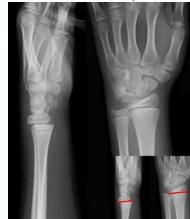

Injured and uninjured wrists after premature physeal closure

Asymmetrical Physeal Affection

- Seen on x-ray

- One side grows more than the other

- Causing an increasing deformity

- Oblique Park-Harris growth arrest/recovery line (white arrows)